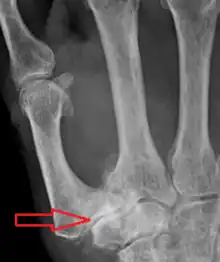

TMC OA severity was classified by Eaton and Littler which can be simplified as follows:[21][22]

Stage 1:

- slight widening of the joint space

- < 1/3 subluxation of the joint (in any projection)

Stage 2:

- Osteophytes, < 2 mm in diameter, are present. (usually adjacent to the volar or dorsal facets of the trapezium)

Stage 3:

- Osteophytes, > 2 mm in diameter, are present (usually adjacent to the volar and dorsal facets of the trapezium)

- Slight joint space narrowing

Stage 4:

- Narrow joint space

- Concomitant scaphotrapezial arthritis

A simpler classification is no arthritis, some arthritis, and severe arthritis.[23] This simpler classification system omits the potentially contradictory details of the Eaton/Littler classification and keeps scaphotrapezial arthrosis separate.